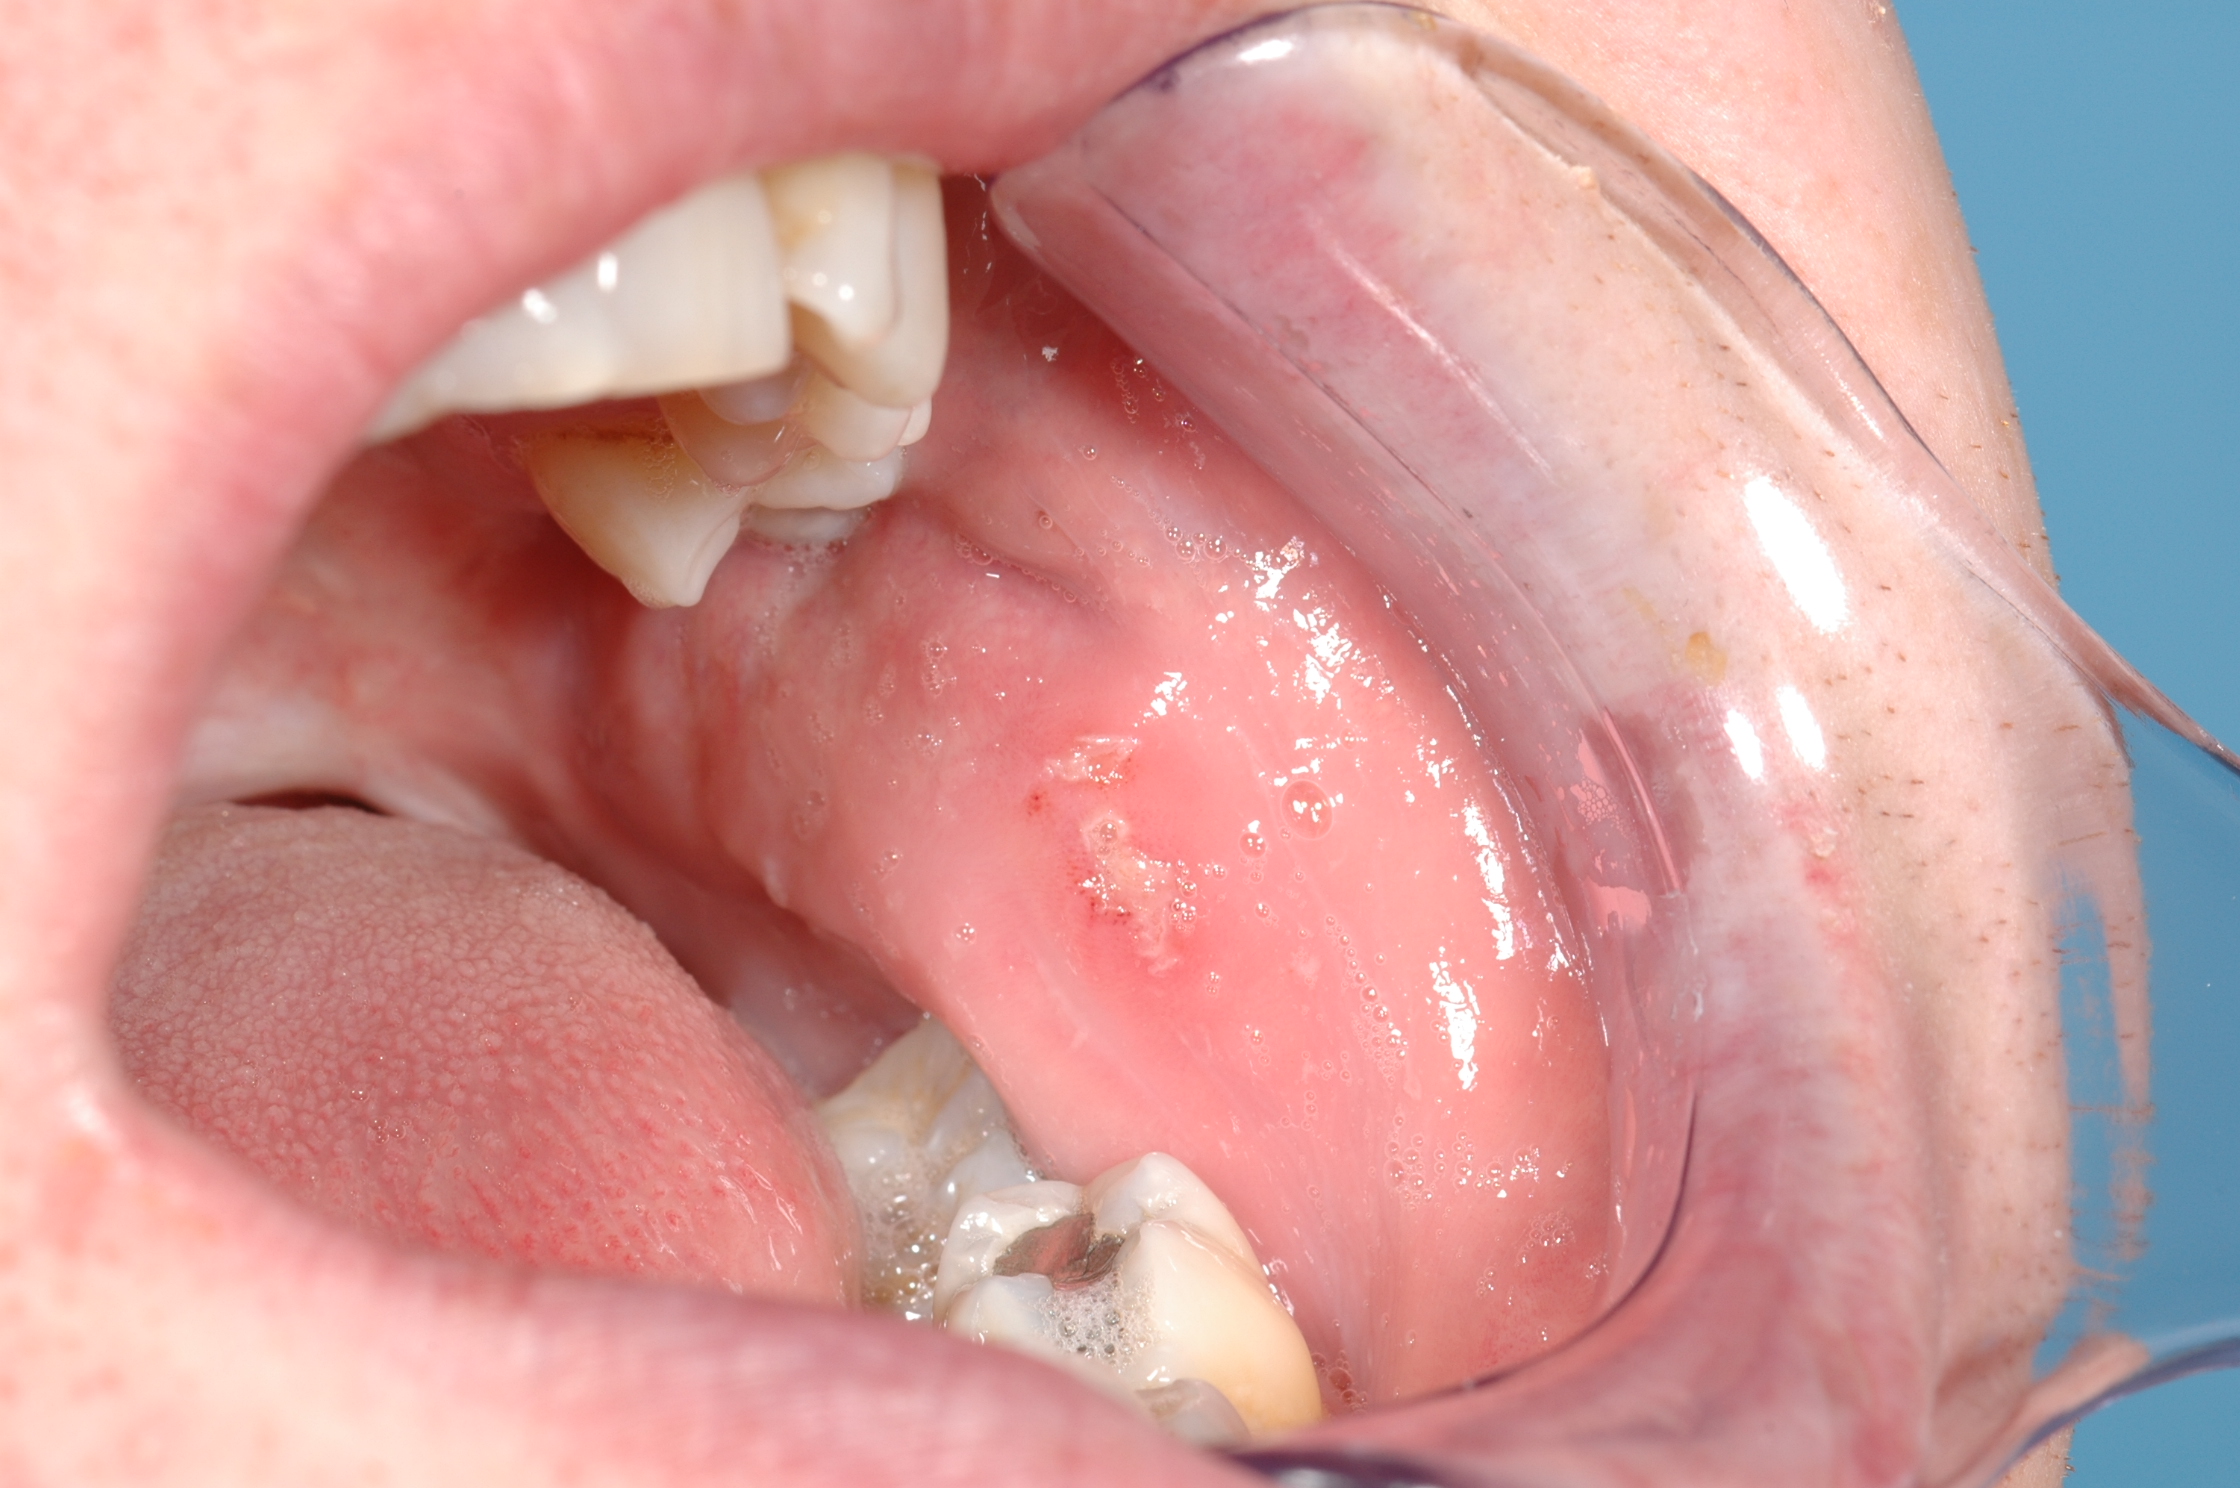

Recurrent mouth ulcers (Figure 1), be they minor or major lesions, have one aspect in common: there is considerable overlap between the detective work of arriving at a diagnosis and identifying underlying causes, and the resulting treatment paths.

The short-term view of the treatment / management of acute minor aphthous ulcers needs to focus on the prevention of superinfections and pain relief. This typically includes the use of chlorhexidine mouthwash and general attention to optimal oral hygiene, a range of analgesics (including topical applications, such as benzydamine mouthwash) and/or topical steroid applications such as hydrocortisone gel. The typical appearance of a healing aphthous mouth ulcer is depicted in Figure 2.